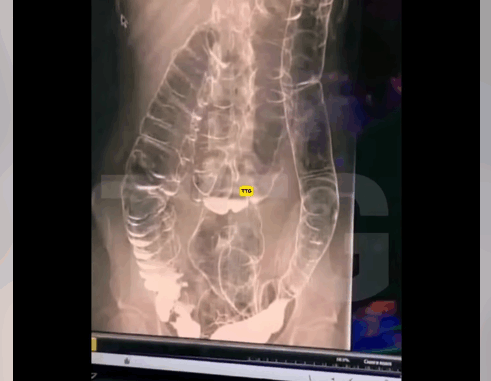

A startling X-ray photo of a woman who experienced two weeks of constipation shocked doctors.

Unable to accommodate the excessive buildup of waste, her colon enlarged significantly, reaching up towards the chest and close to the heart.

The chronic constipation led to the colon’s folds – that are vital to its functionality – to disappear.